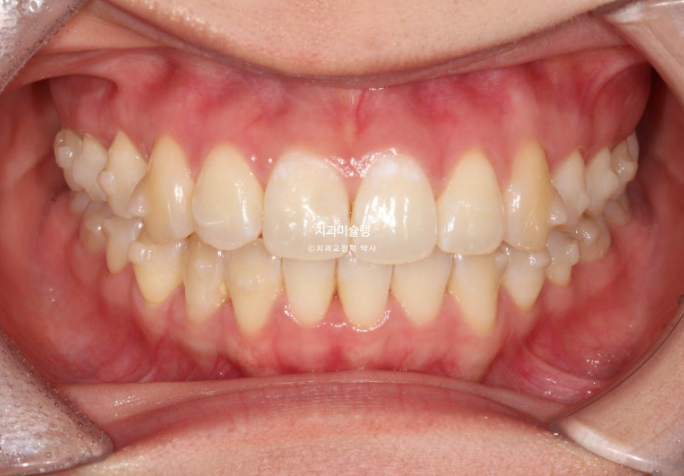

중심선이 약 3mm 어긋나 있습니다.

덧니가 보이고 파란화살표에 소구치에 가위교합도 있습니다.

중심선은 정확히 맞고

어금니 교합은 물샐틈 없는 1급 교합관계 입니다.